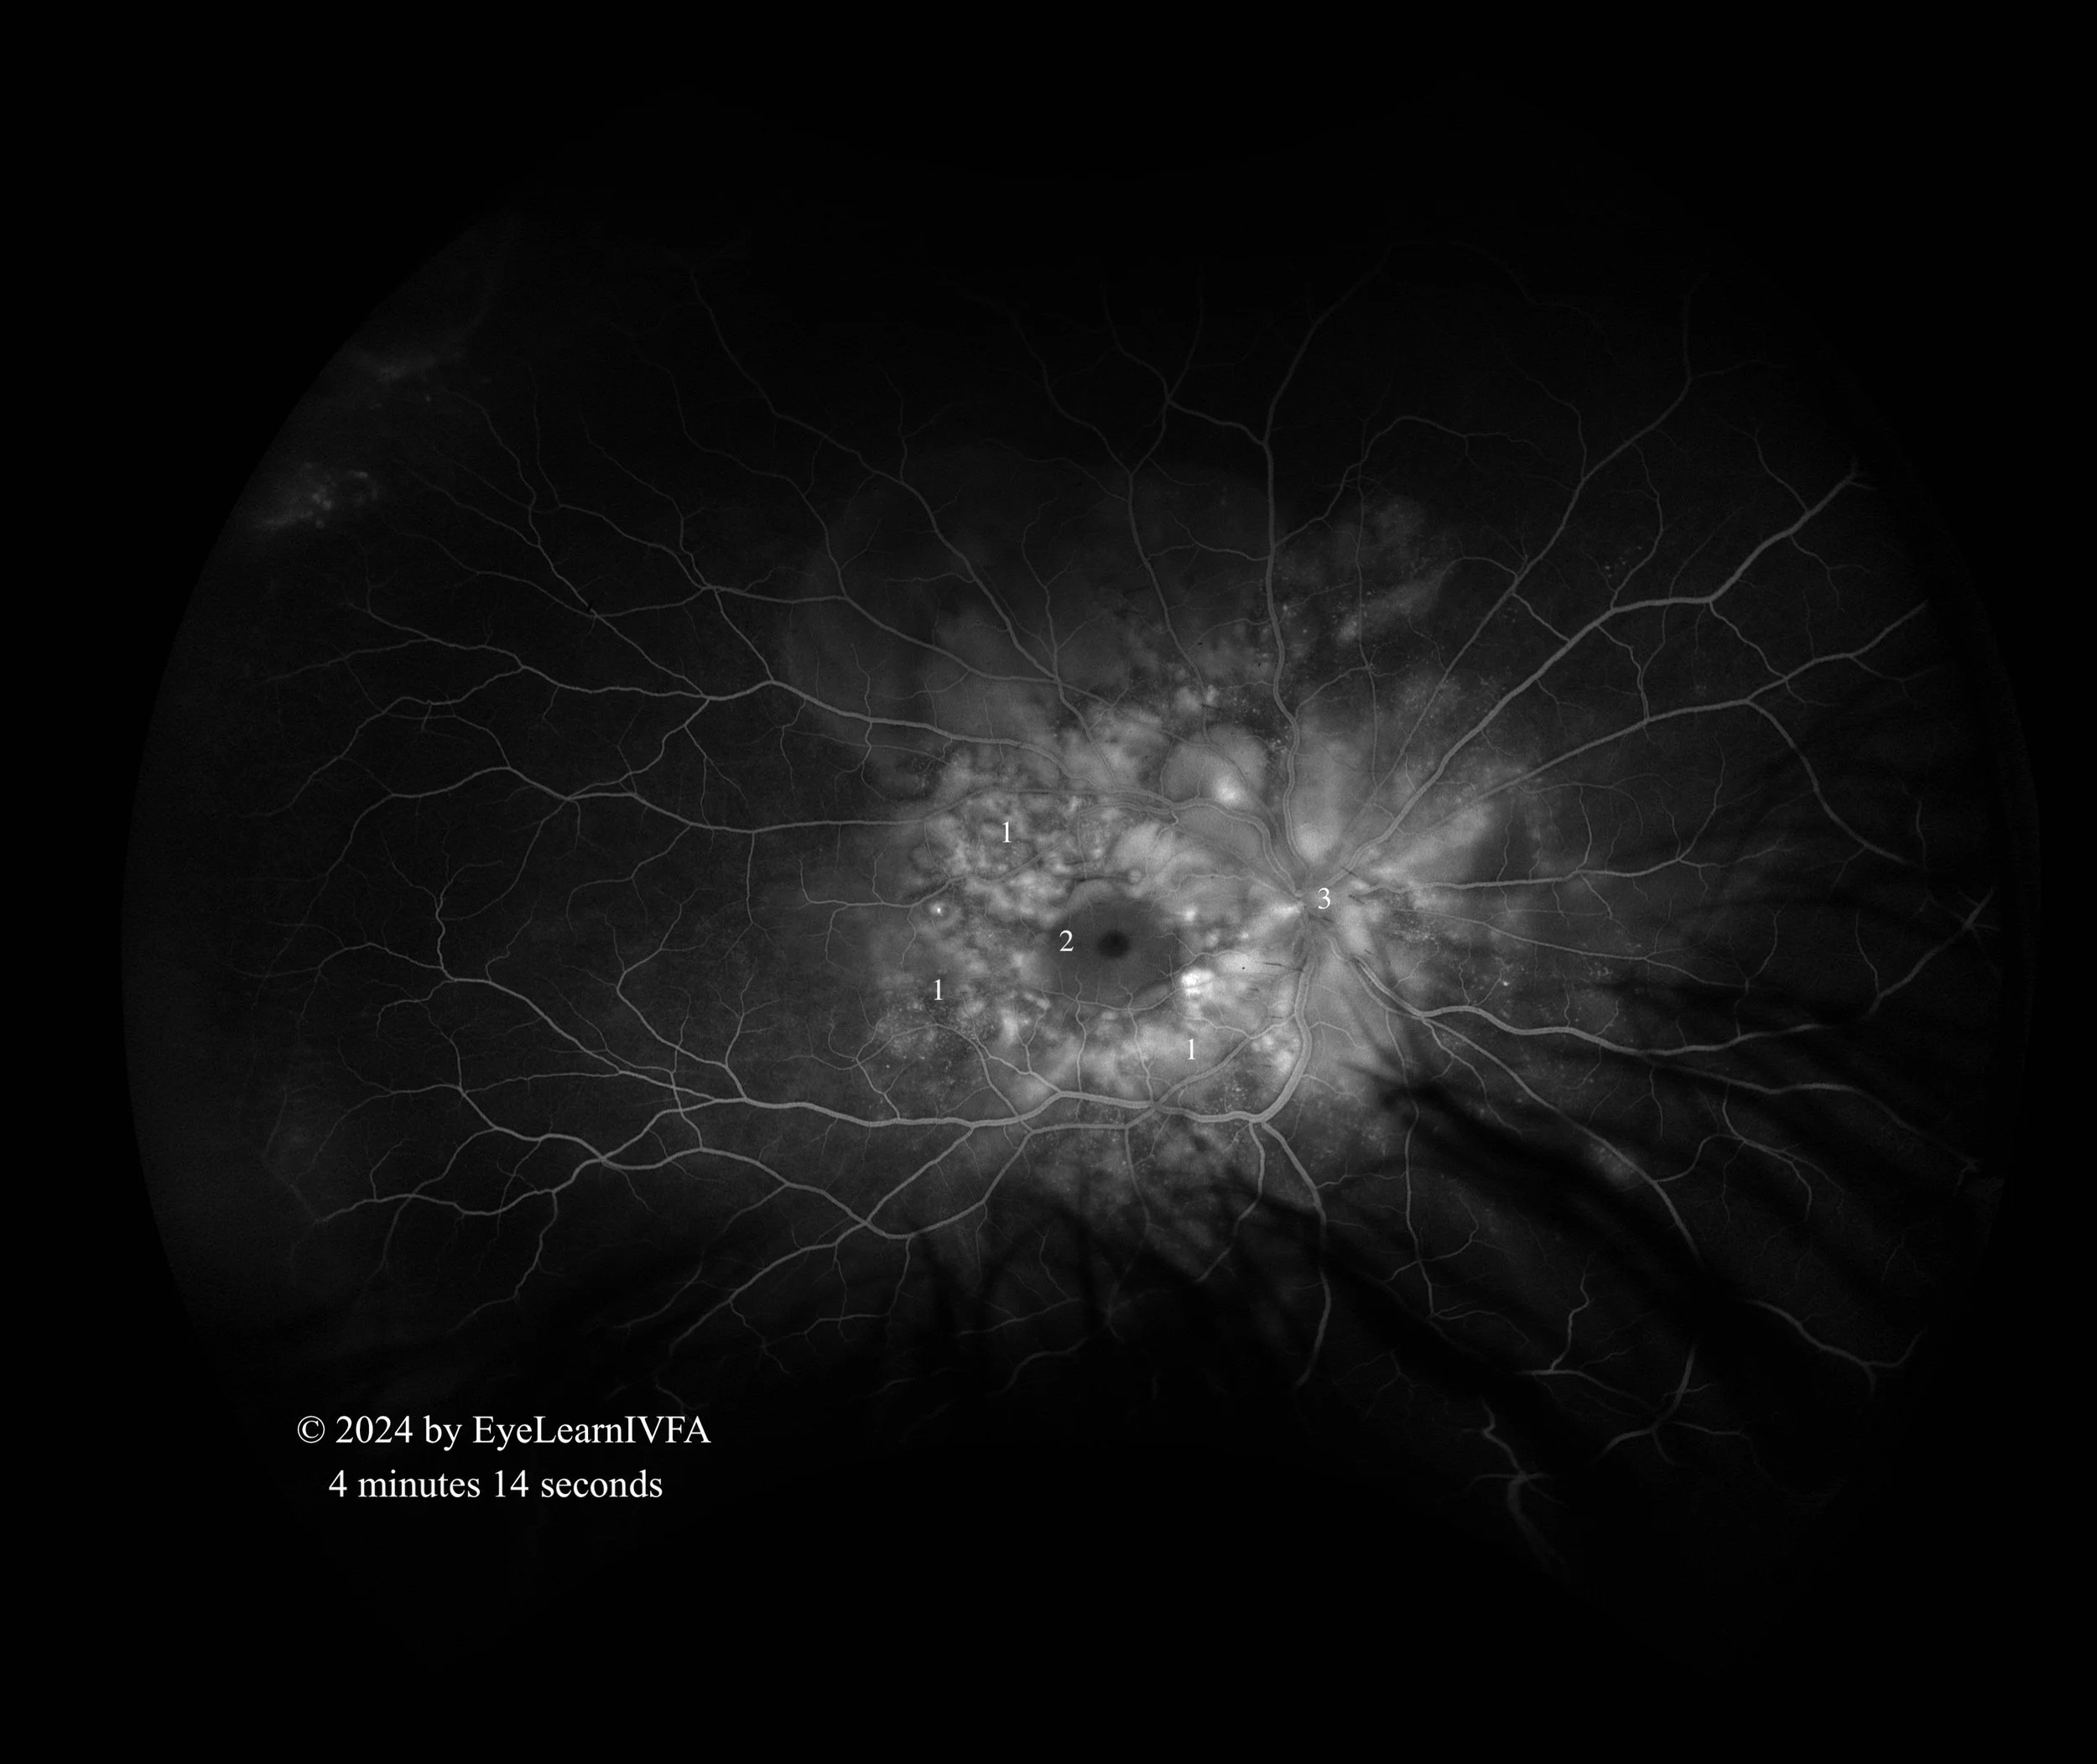

• IVFAs after 4 minutes in both eyes

Late Phase.

Key Features:

• Continued pattern of pinpoint areas of hyperfluoresence around nerve and macula - more obvious “starry sky” appearance (1)

• In the right eye, there is hypofluorescence over the macula secondary to serous subretinal fluid (2).

• Presence of hyperfluorescent optic nerve OS, with a ring of hypofluorescence (3).